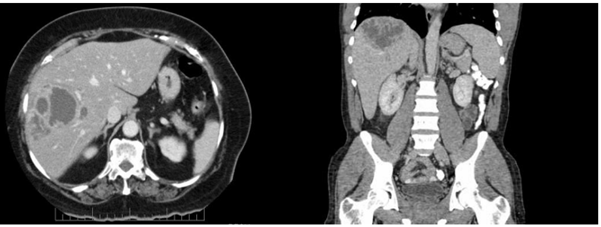

Paciente de 32 anos, sexo feminino, procurou o pronto-socorro por fraqueza, febre vespertina de até 39 ºC e dor em hipocôndrio direito há 4 semanas. Retornou da viagem de 1 semana ao Pará (proximidades de Santarém) 2 dias antes dos sintomas iniciarem. Exame físico: bom estado geral; anictérica; febril; hidratada; auscultas cardíaca e pulmonar normais; abdome doloroso à palpação em hipocôndrio direito; fígado palpável a 3 cm do rebordo costal direito; baço não palpável; algumas lesões de pele nas pernas. Exames laboratoriais: hemoglobina 11,9 g/dL; leucócitos 19.000/mm3; TGO 45UI/L; TGP 38UI/L; fosfatase alcalina 304 UI/L; gama-glutamiltransferase 268 UI/L; proteína C reativa 135. Tomografia computadorizada de abdômen apresentando a imagem a seguir:

Em relação ao caso, além de coletar hemoculturas, a conduta adequada é: